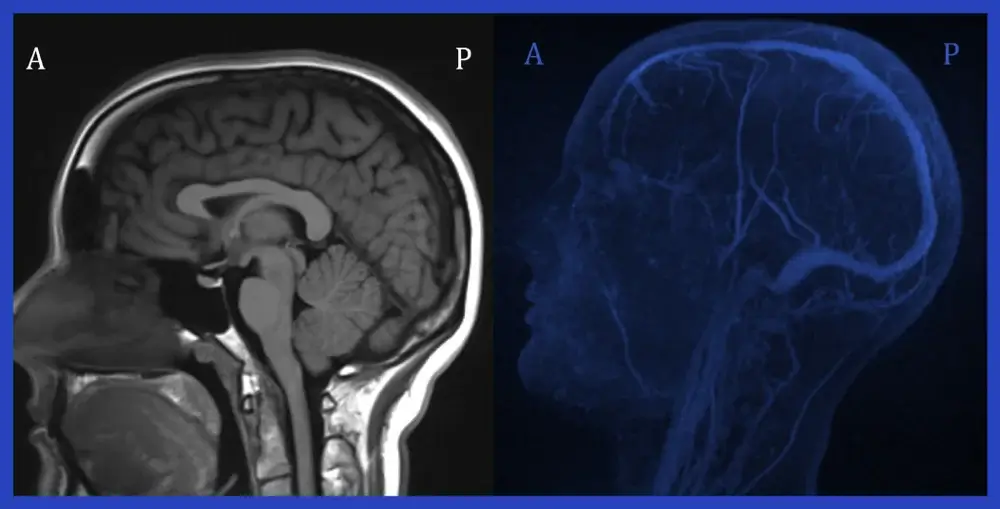

Magnetic Resonance Imaging (MRI) has become a critical tool in modern medicine, providing high-resolution images of the body’s internal structures. While MRI is typically known for its ability to diagnose conditions affecting soft tissues, bones, and organs, it also plays a vital role in visualizing blood vessels.

But does MRI show blood vessels clearly? The answer is yes — and more precisely than many might realize. Blood vessels are integral to many physiological processes, and imaging them effectively is crucial for diagnosing various medical conditions. What is an MRI scan used to diagnose? MRI scans are used to diagnose a wide range of conditions, including vascular diseases, strokes, aneurysms, and blood clots, providing critical insights into the health of the circulatory system.

Yes, MRI can show blood vessels and provide detailed images of the vascular system. However, a standard MRI does not directly visualize blood vessels in the same way it shows organs and soft tissues.

For blood vessel imaging, specialized MRI techniques, such as MR Angiography (MRA), are used. These techniques are designed to produce high-quality images of the blood vessels, showing their structure and identifying any blockages, narrowing, or abnormalities.